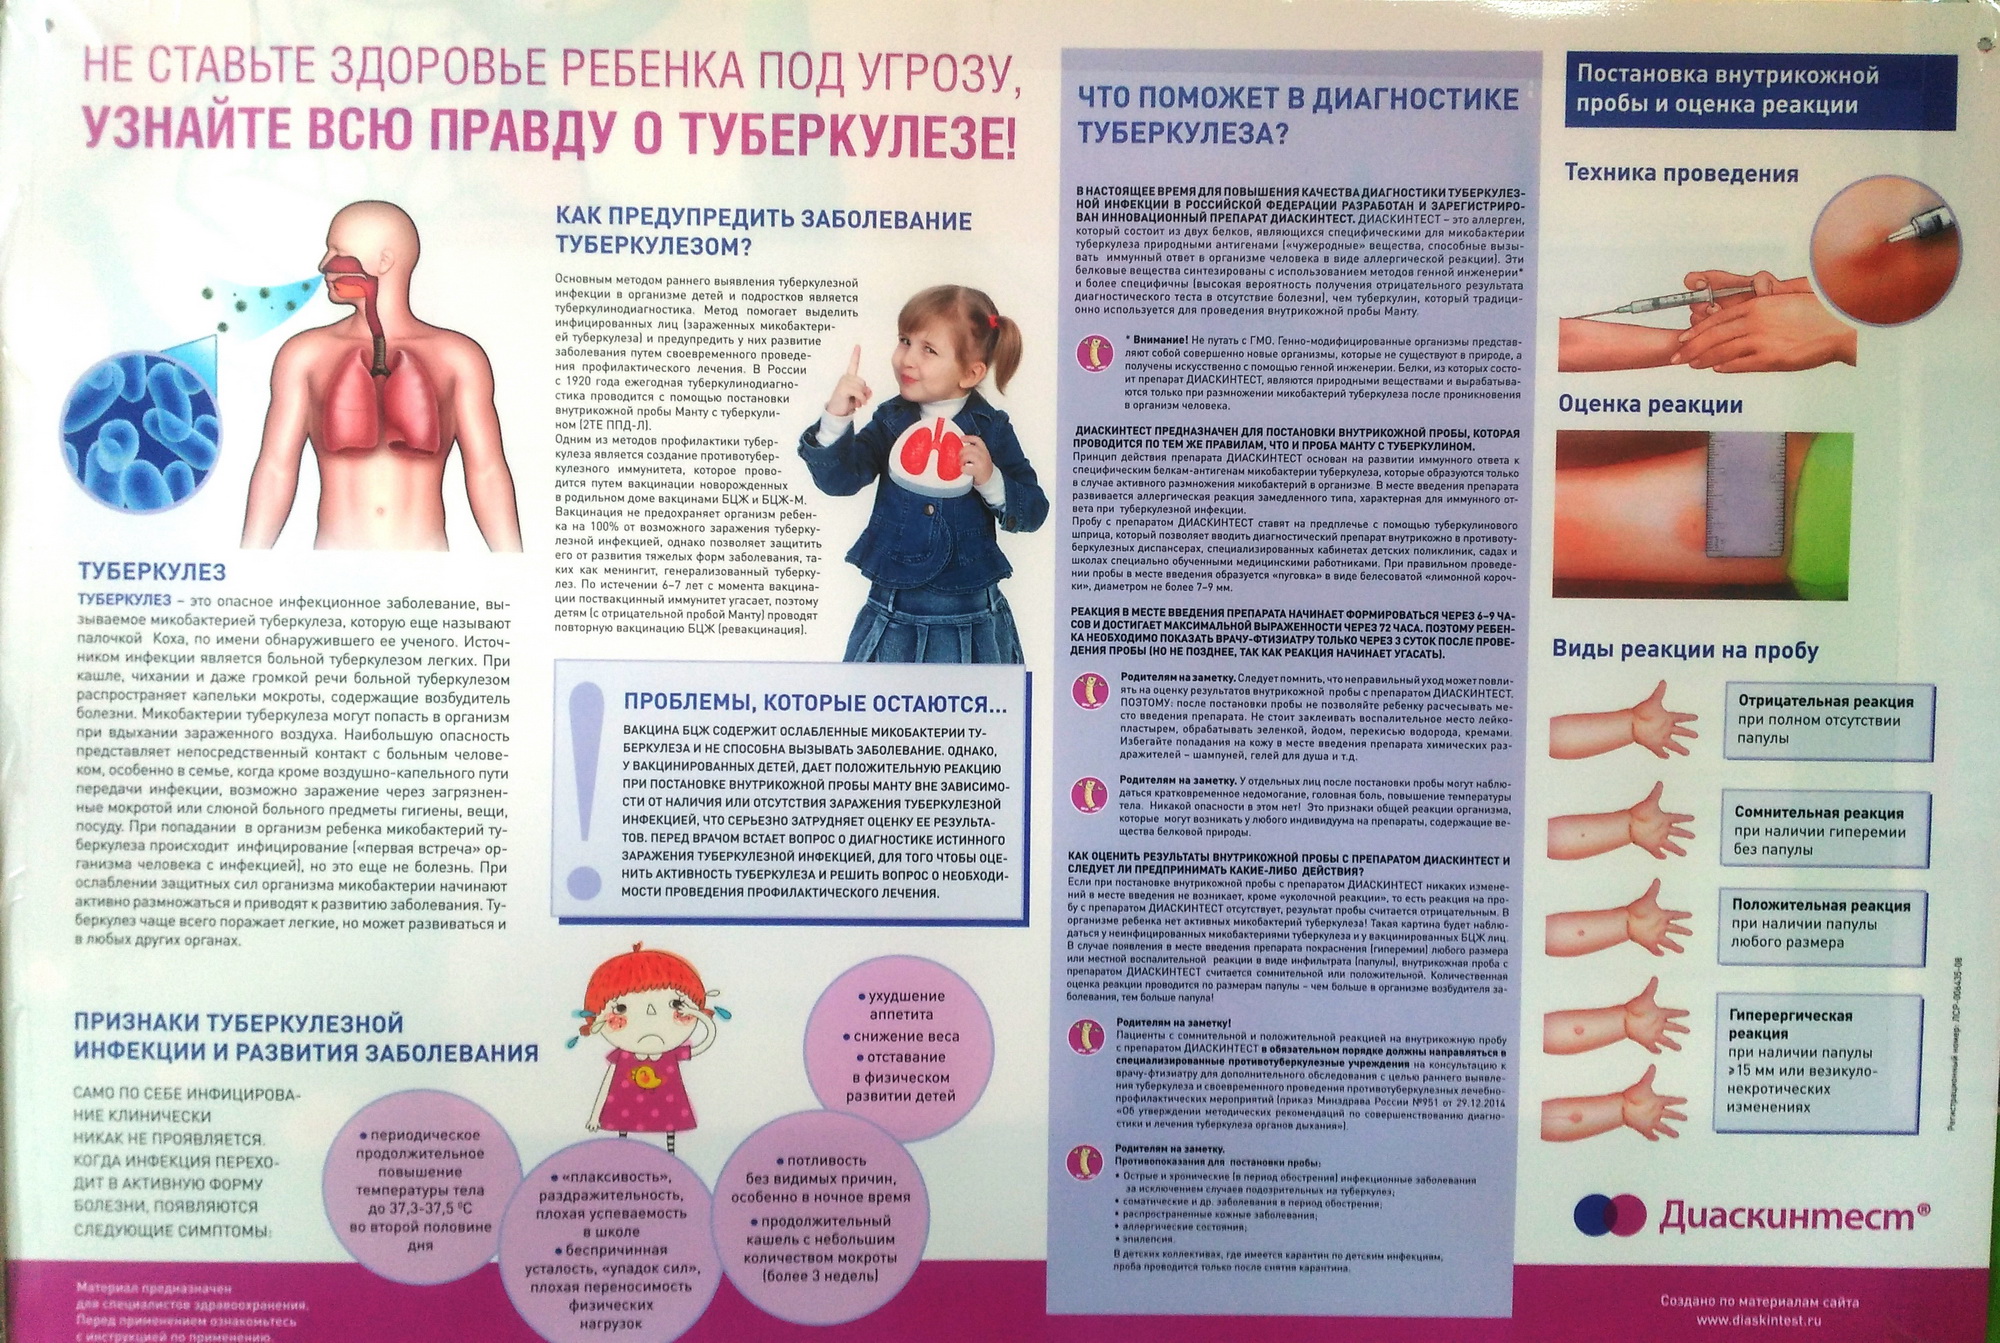

Симптомы и признаки туберкулеза: как распознать заболевание

Раздел: Визуальные уроки